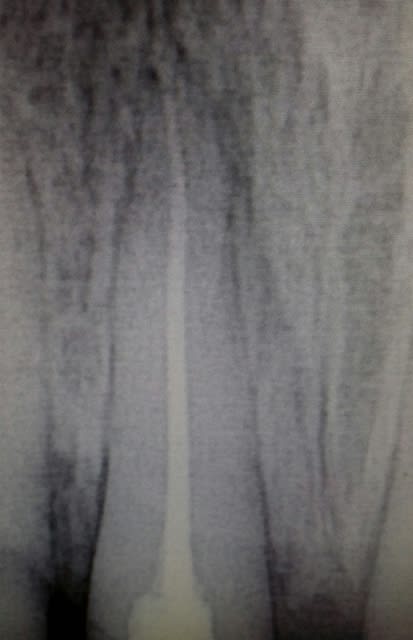

un profile tout neuf bien fracture au niveau du mandrin dans une 21 d un jeune a gros canal.

au niveau du mandrin donc entierememnt visse dans le canal jusqu a l apex.

le niveau de fracture environ au quart coronaire. meme si je mettais la dent a plat j y aurais pas acces.

je passe a cote jusqu a mi racine.

Du glyde un insert diamant et c est parti.

Et voila

j ai ete aide par l usage de la trousse de gonon ou

une visseuse jaune a cree un espace autour du profile.

les inserts et le glyde ont agi ensuite